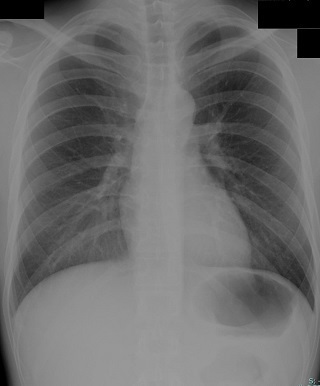

一般撮影

放射線を使う検査の中で、みなさんが一番に思い浮かべるのがこの検査ではないでしょうか。

通常、病院等で身体の撮影に使われている放射線は、いろんな放射線の種類がある中でも、X線と呼ばれているものです。そのX線を利用して撮影します。胸部、腹部、頭部、脊椎、手足等いろんな部位を短時間で検査することができます。

妊娠中の方、又は妊娠の可能性のある方は検査の前に担当者にお知らせください。